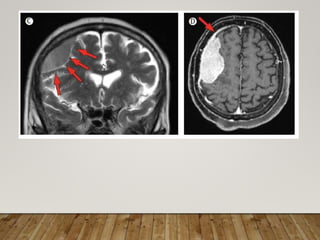

INVESTIGATIONS-RADIOLOGICAL

• Meningiomas can be diagnosed by MRI and additional CT

in most cases

• Using these classic criteria, MRI has a sensitivity and

specificity of 98% and 97%, respectively.

• They usually present as solitary round tumours, with close

contact to the dura mater and strong enhancement after

contrast injection.